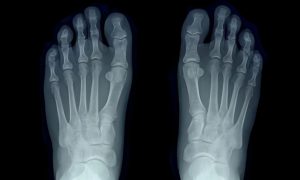

– Iby’amagufwa (Bones): kumenya imvune, ibikomere cyangwa indwara zifata amagufwa.

- Gusuzuma amagufwa (imyivumbagatanyo, imvune, arthritis)